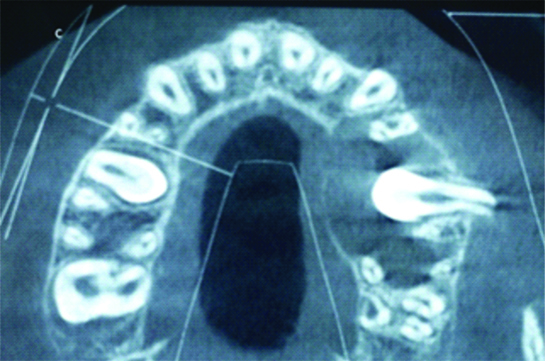

A 12 Years eight-month-old female patient reported in Department of Paediatric and Preventive Dentistry with a chief complain of pain and swelling on the posterior palate since three days. Medical history of the patient was taken and it was unremarkable. The pain was dull and gnawing. There was a discharge of blood-stained fluid from the swelling after brushing one day before, after which there was some relief from the pain. The Patient’s parents gave a history of treatment done for deciduous maxillary left second molar in same department, It was concluded through provided documents that pulpotomy followed by silver amalgam restoration was done three years back. Palatal Swelling concerning deciduous maxillary left second molar was present. The swelling was soft and tender, extending from the mesial surface of the permanent maxillary left first premolar till the mesial surface of the permanent maxillary left first molar. The swelling size was 3×2 cm [Table/Fig-1a]. Additional findings were increased overjet of 6 mm and maxillary and mandibular teeth are malaligned [Table/Fig-1b,c]. After clinical examination and history taking, provisional diagnosis of radicular cyst or dentigerous cyst was made. IOPA, Occlusal radiograph and CBCT (Panoramic View) were advised, which showed a well-defined radiolucency involving the apices of maxillary left first premolar, apices of the deciduous maxillary left second molar and an horizontally impacted permanent maxillary left second premolar [Table/Fig-2a,b and c]. To delineate the exact extent of the cystic margins CBCT was advised. In sagittal view [Table/Fig-3a], extension anteriorly was from distal surface of left maxillary canine, up till mesial surface of the maxillary left second molar posteriorly, In frontal view of CBCT [Table/Fig-3b], the cyst was seen invading the maxillary antrum and also the floor of the nose, and In transverse view [Table/Fig-3c], horizontally impacted permanent maxillary left second premolar with root facing buccally was seen. Additionally cortical expansion along with the breach in continuity can be appreciated in the palatal aspect of transverse section in CBCT. Exploratory puncture biopsy was performed, which produced a bloody liquid. Parents were narrated the treatment options of surgical removal of whole of the cyst which would harm the vital adjacent structures and marsupialization technique which was a conservative treatment. Pros and cons of both the treatments were explained. Marsupialization was opted by patient as well as the doctor for its relative conservative approach. Consent was taken from both patient and parents followed by extraction of the left maxillary deciduous second molar [Table/Fig-4a] and removal of parts of the lesion for histopathology report. The microscopic findings of cystic lining showed thick stratified epithelium cells which were secondarily infected also cystic wall showed fibrous tissue [Table/Fig-4b]. Based on the clinicopathological findings, the final diagnosis was made as a dentigerous cyst which was secondarily infected. Benn A et al., carried out a clinicopathologic study on dentigerous cyst of inflammatory origin [1]. They found all of the cysts were moderately or intensely inflamed and were lined predominantly or entirely by nonkeratinized stratified squamous epithelium that in some cases was markedly hyperplastic and exhibited anastomosing rete ridges mimicking radicular cysts. Therefore, the differentiation form radicular cyst was not possible.

Transverse view: horizontally impacted permanent maxillary left second premolar with root facing buccally was seen, Also cortical expansion was evident in CBCT when viewed in all the three views.